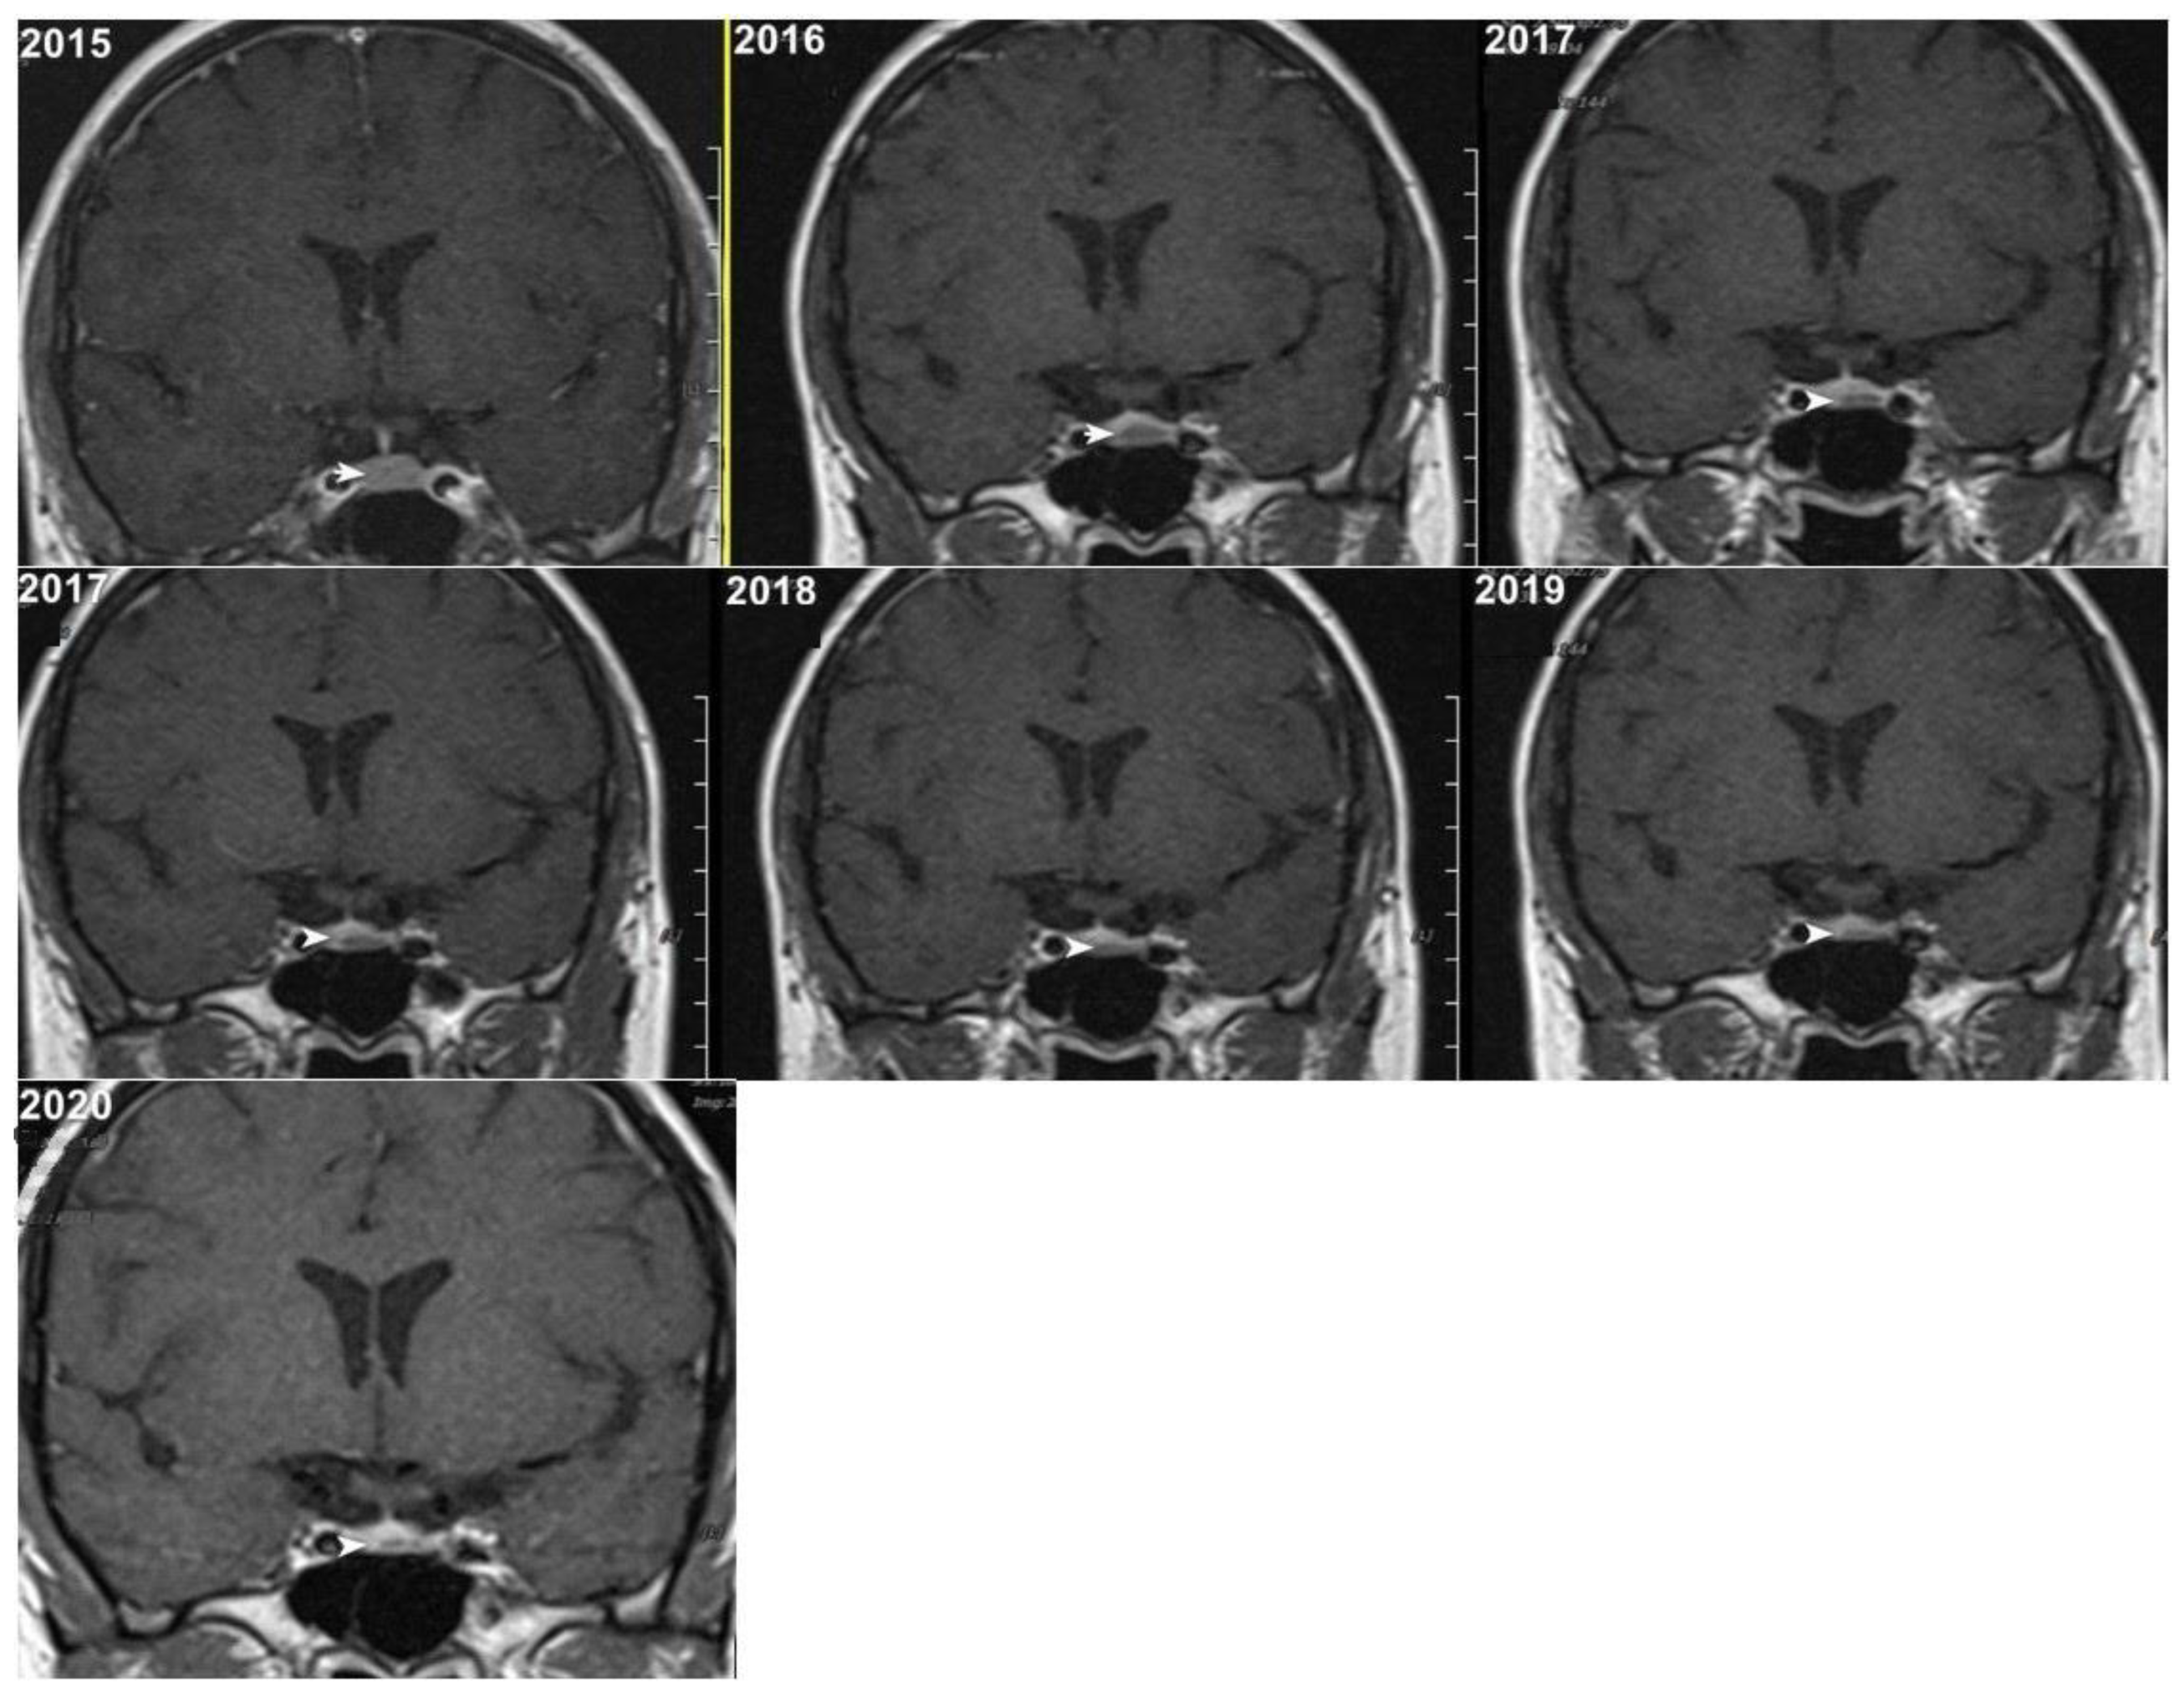

Although, the main cohort contained patients referred between 2020 and 2024, Figure 2, Figure 3 and Figure 4 shows a representative case with historical scans (2015–2020), retrieved from PACS, to demonstrate temporal stability. No evidence of recurrence of tumors in any of the nine who underwent resection of macroadenomas during this period was seen.

Figure 3.

Representative T1W coronal images (2015–2020) of a stable microadenoma (arrows) of a 33 Y/O woman. In the 5 years of follow-up, no size change can be seen.

Moreover, repeated exposure to gadolinium is associated with the deposition in basal ganglia and the dentate nuclei of the cerebellum. This deposition results in an increased signal intensity seen in T1-weighted imaging that has raised concerns concerning potential long-term neurological effects. These safety concerns are thus especially important in the case of patients with microadenomas who may require repeated MRI surveillance [38,39]. Given the fact that patients with microadenoma may be exposed more frequently to MRI with contrast, our study investigated conventional MRI and dynamic imaging for diagnosis and follow-up in patients with pituitary microadenomas undergoing MRI at our institution. We also evaluated the change in size of microadenomas in follow-up MRI studies and the necessity of injecting contrast media in monitoring this set of patients (Figure 2, Figure 3 and Figure 4).